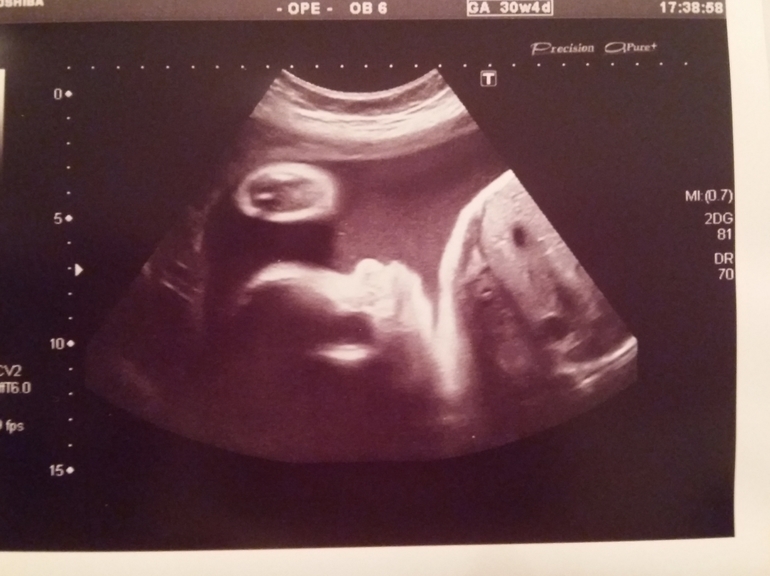

Покупки сегодняшние, УЗИ 30,4 недель. +фото

Приданое для малышаСегодня после работы ( да, да, я работаю ещё))) мы с мужем и дочерью решили пройтись по магазинам и купить мне платье на выписку( я никак не решусь, потому что оно приталенное, но очень красивое, боюсь, что не выйду я с роддома со своим размером s и плоским животом...) недоходя до отдела с этим платьем, мы завернули в детский мир ( я запищала, что забыли купить горку в ванночку, а так уже все все все куплено) ну, ну ( когда шли на кассу, чуть не забыли купить ту самую горку, из-за которой и зашли ). Так и не дошли мы до магазина с платьем. По УЗИ все хорошо, растем, губки надуваем, положение продольное головное))))) вес 1498г ( на этом аппарате +-55г) по УЗИ, как и по месячным 30-31 недели.

Далее фото